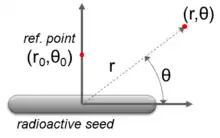

The calculation of radiation dose from radioactive seeds is crucial in the planning and administration of brachytherapy treatments. Most modern calculation are done using the formalism published by the American Association of Physicists in Medicine.[83] For the geometry in figure 1, this formalism uses five parameters.

- Strength of the source: How much radiation is being emitted by the seed, expressed as air kerma strength and denoted by .

- Dose rate of the source: How much dose the seed will deliver to the reference point over a certain period of time, denoted by .

- Geometry factor: How the shape of the seed will affect the dose at points away from the reference point, denoted by .

- Anisotropy function: How the much radiation will be stopped before passing out of the seed, denoted by .

- Radial dose function: How the radiation will interact with the material surrounding the seed, denoted by .

The equation which links these parameters is,